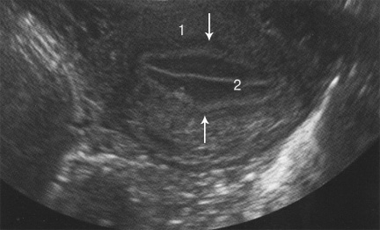

Применение современных ультразвуковых приборов позволяет сегодня не только оценить толщину эндометрия, но и дать его точную качественную характеристику, т.е. оценить его ультразвуковую структуру. Нами проведен анализ эхографической картины эндометрия у женщин с НБ. У обследованных женщин с НБ и контрольной группы наблюдались следующие эхографические картины эндометрия: 1. трехлинейная картина; 2. нетрехлинейная картина. При трехлинейной картине выявлялся гипоэхогенный эндометрий с хорошо очерченными гиперэхогенными наружными краями и центральной эхогенной линией (рис.2). При нетрехслойной картине выявлялся изоэхогенный эндометрий с невыраженной центральной эхогенной линией или ее отсутствием.

Рис. 2. Трансвагинальная эхограмма трехслойной картины эндометрия (поперечное сканирование): 1. матка, 2. эндометрий